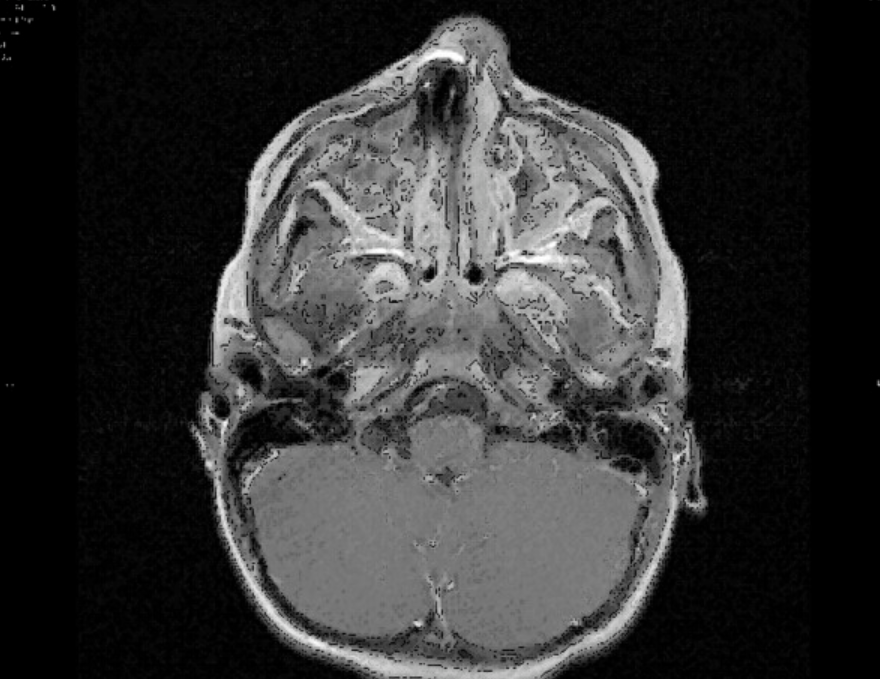

This is not something you want to see on an MRI. The patient was a 3 y.o. boy with a suspected upper respiratory tract infection. But why has most of his face disappeared from the scan?

Luckily the radiologist realised immediately what was going on and terminated the procedure. The shadow on the image suggested a ferromagnetic foreign body somewhere in nasal or oral cavities - which in the powerful magnetic field of an MRI scanner might have done serious damage.

The child had been given a general anaesthetic for the MRI - which was fortunate, because he had resisted all attempts to examine him at close quarters while conscious. Now the ENT physicians found and easily removed a small button cell from his nasal cavity.

Interestingly, a second MRI showed that there was still some ionic material left behind in the mucosa - the shaded areas corresponding to the right nasal cavity. The symptoms quickly resolved with antibiotics and the child made a good recovery.